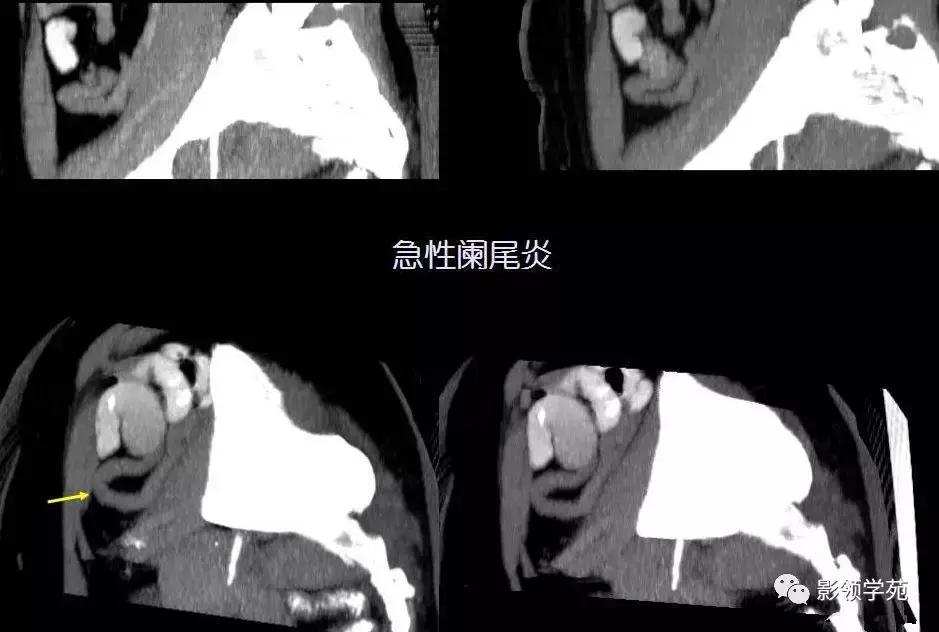

(二)急性阑尾炎:大多数病人起病时先有中上腹持续性隐痛,数小时后腹痛转移至右下腹,呈持续性隐痛,伴阵发性加剧。少数病人起病时即感右下腹痛。中上腹隐痛经数小时后转移至右下腹痛是急性阑尾炎腹痛的特点,约占70%至80%。可伴恶心、呕吐或腹泻。重者可有发热、乏力、精神差。右下腹固定压痛点是诊断急性阑尾炎的最重要体征,典型的是麦氏点(Mc Bunery点)压痛或伴有肌紧张、反跳痛;结肠充气试验、腰大肌试验或闭孔内肌试验阳性不仅有助于诊断,还有助于术前阑尾定位。直肠指检及妇女盆腔检查对鉴别很有必要。